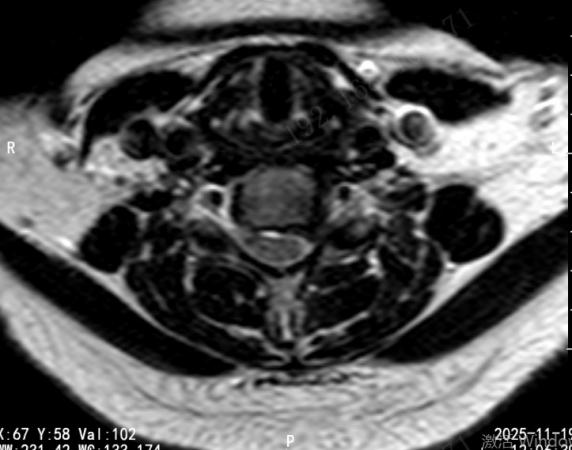

近日,济南市第四人民医院脊柱外科团队成功应用单边双通道内镜技术(Unilateral Biportal Endoscopy,简称UBE),为多位深受神经根型颈椎病折磨的患者实施了微创手术治疗。该技术的成功开展,标志着医院在脊柱微创领域取得了又一突破性进展,为本地及周边地区的颈椎病患者提供了一个更优、更精准的治疗选择。

神经根型颈椎病是由于颈椎间盘突出、骨赘增生等原因压迫了神经根,导致患者出现颈部疼痛,一侧上肢放射性麻木、疼痛、无力等症状,严重时甚至影响抓握、行走,生活质量大打折扣。

“UBE技术可以理解为给医生的眼睛和手装上了一双‘延长筷’,” 医院脊柱外科主任韩建龙教授形象地解释道,“通过两个仅约1厘米的微小切口,一个通道放入高清内镜,提供清晰放大的手术视野;另一个通道放入各种精密的操作器械。医生能够在清晰的视野下,精准地去除压迫神经的突出物或骨赘,彻底解放被‘卡压’的神经根,同时最大程度地保护了正常的肌肉组织和骨骼结构。”